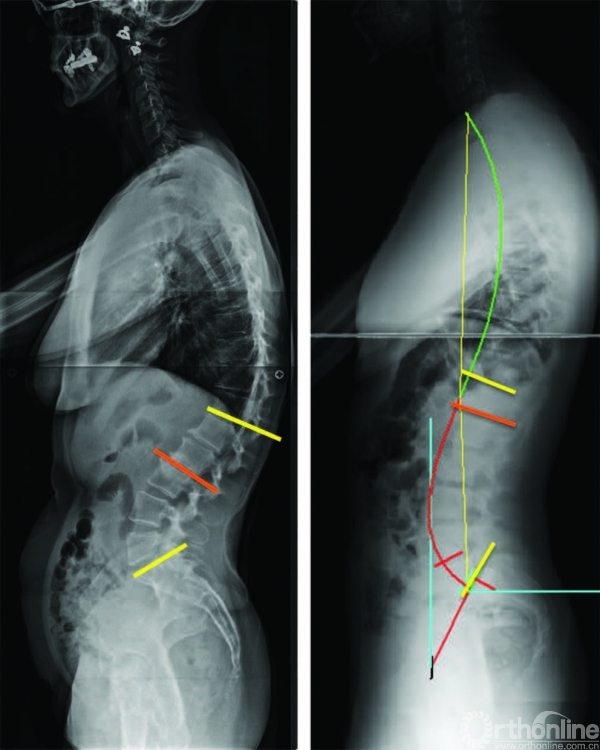

图 6-6 全脊柱侧位X线

片中前凸长度的影响在左侧,有一个短节段腰椎前凸,前凸主要集中在少数几节脊椎。注意前凸曲线的上端在L3。在右边,有一个较长节段的腰椎前凸